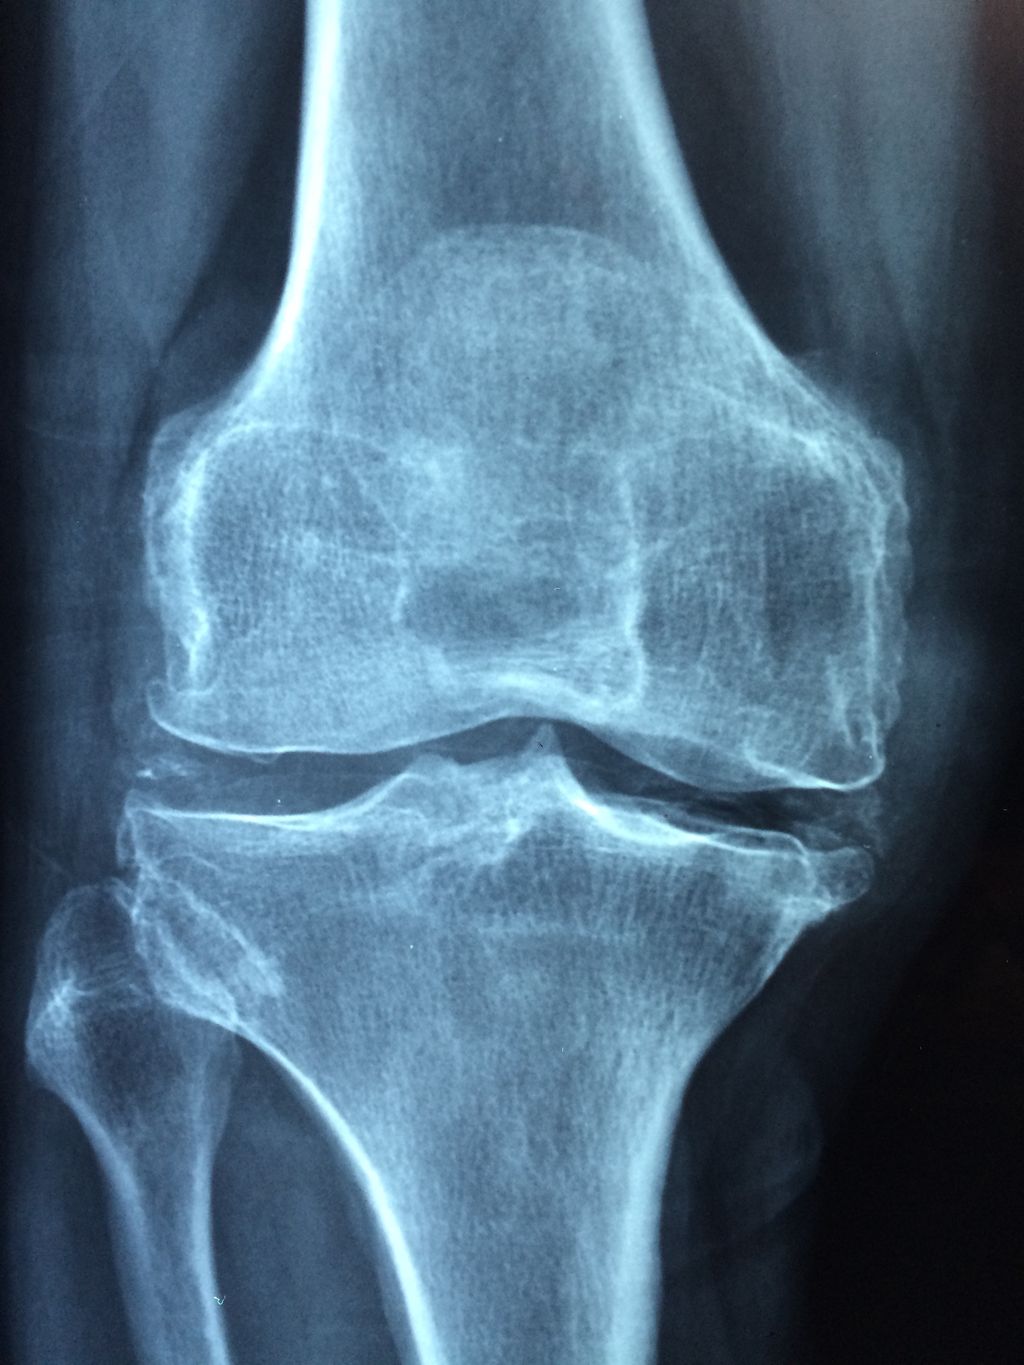

Degenerative Changes

As we delve into the causes of meniscus injuries, we must consider the impact of degenerative changes. Over time, the menisci can deteriorate due to aging and wear-and-tear, reducing their ability to cushion and stabilize the knee joint. This process is often asymptomatic initially but may eventually lead to pain, stiffness, and limited mobility.

Osteoarthritis is a common condition associated with meniscal degeneration. The breakdown of cartilage that characterizes osteoarthritis can exacerbate the weakening of the meniscus, making it more susceptible to tears even with minor trauma.